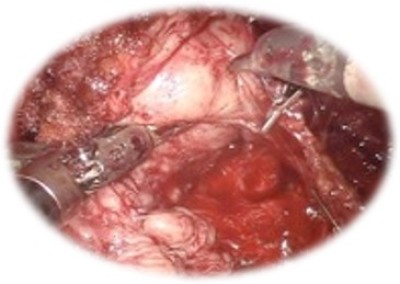

Prostatectomia radicală robotică:

• Standardul de aur în tratamentul chirurgical al cancerului prostatic localizat

• Presupune îndepărtarea glandei prostatice împreună cu veziculele seminale și ganglionilor regionali

• Rata complicațiilor intra și postoperatorie redusă, cu sângerare minimă